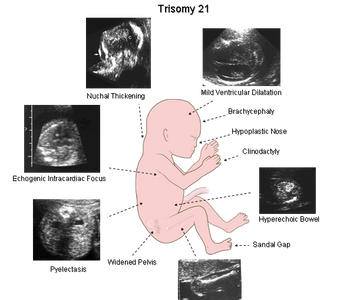

In humans, there are 23 types of chromosomes and most people have a pair of each one of these chromosomes (therefore a total of 46 chromosomes). In trisomy, there are three rather than two of a particular chromosome (total of 47 chromosomes). The most common trisomies are those of chromosomes 21, 18 and 13.

There are a number of potential nonstructural or minor markers which may be seen at the time of the fetal anatomic scan around 20 weeks. These findings may sometimes indicate an underlying chromosome abnormality, like Down syndrome or other fetal abnormality, but are most often seen as a normal variant. As an isolated finding, these findings usually do not significantly change the risk. For additional reassurance, you might choose an NIPT test to confirm the chromosomes are normal.

These include:

At the time of a 12 week (11 to 13+6) weeks) nuchal translucency (NT) ultrasound scan (offered to all pregnant women), you will also be offered a blood test measuring human chorionic gonadotropin (HCG), which tends to be increased in affected fetuses, and plasma associated protein A (PAPPA) which tends to be decreased in affected fetuses with Down syndrome. This test is offered as standard through the NHS. It can detect approximately 85% of major chromosome abnormalities like fetal Down syndrome, but there is also at least a 5-7% chance of a false positive result, in which case genetic amniocentesis or CVS might be suggested.

NIPT (non invasive prenatal testing) is a specialized genetic test of the fetal DNA, usually taken at 10-13 week range. These tests directly analyze fetal DNA fragments circulating in the maternal circulation. They are highly accurate for detecting fetal trisomy 21 (Down Syndrome) and other major chromosome abnormalities. The advantage is both the higher detection rate (99.5%) and the very low false positive rate (less than 0.5%). However, NIPT tests and cost vary with the extent of testing. They are offered to some selected high risk patients in the NHS.